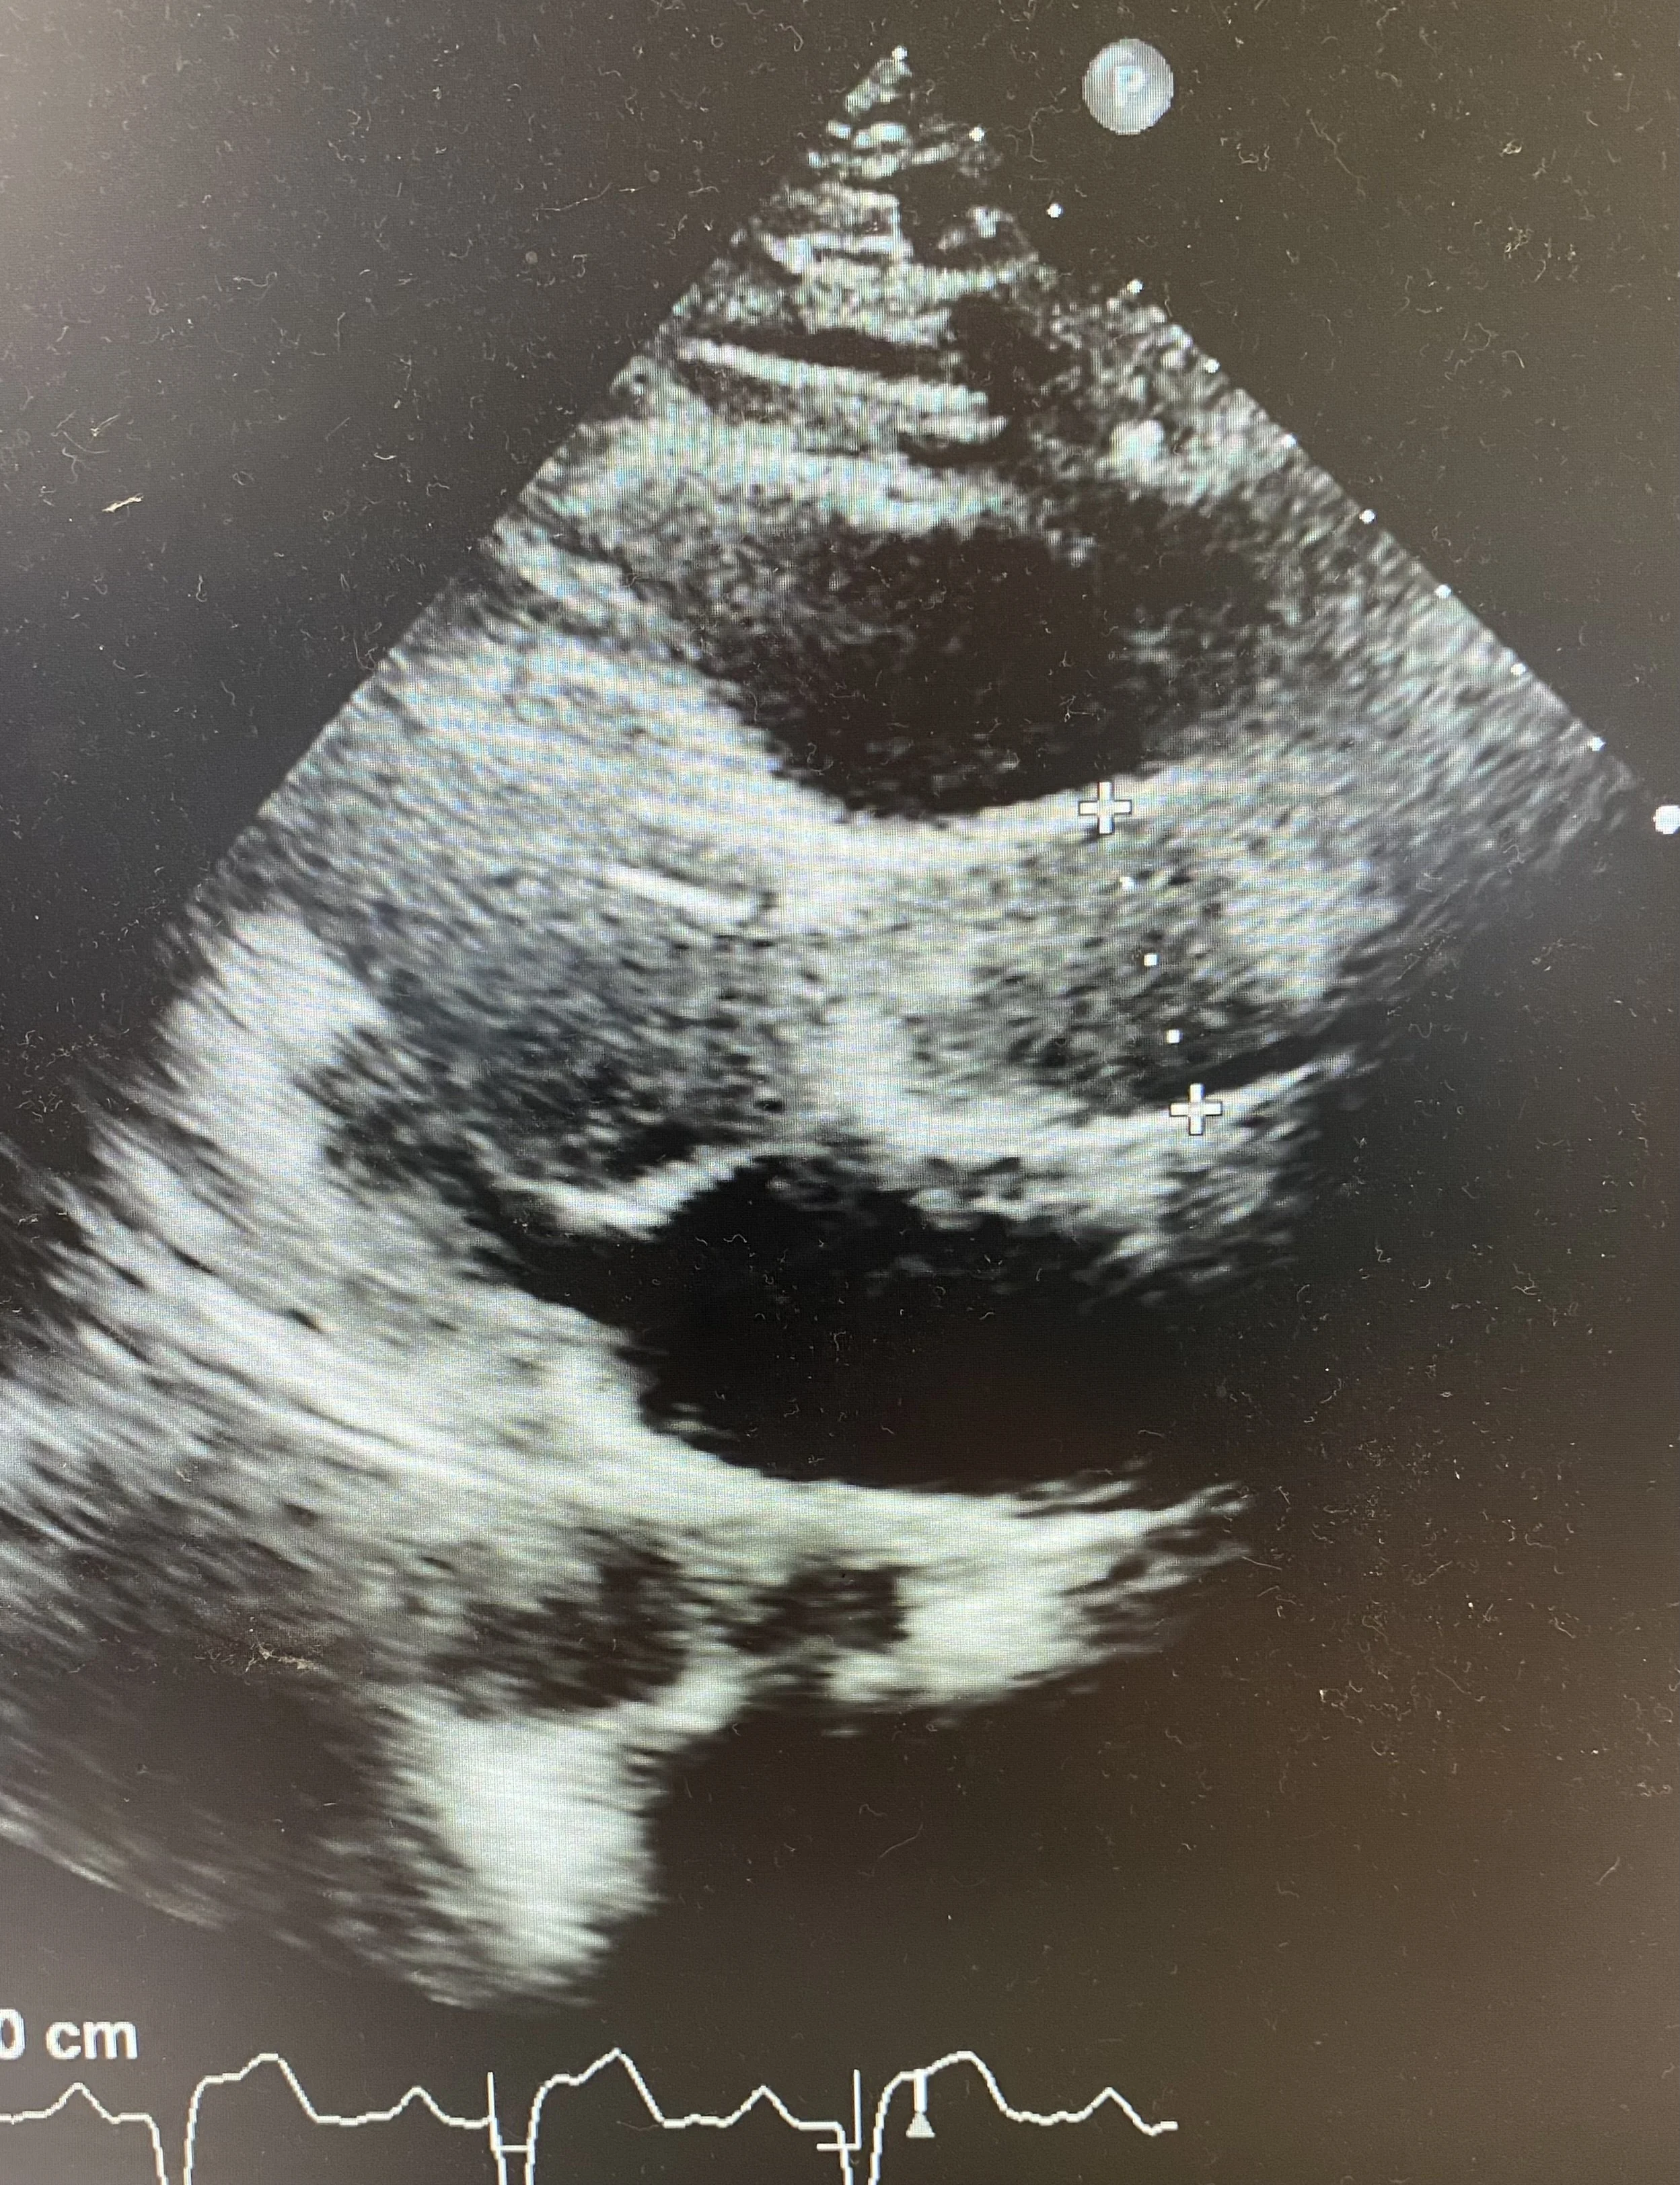

POCUS (shown below) showed a normal size aortic root and ascending aorta. There was no pericardial effusion.

See stills showing measurement of the Aortic Root (top) and the Ascending Aorta (bottom). From the Parasternal long-axis you may need to rotate the probe to open up the aortic root and measure the maximum width. Ensure the ascending aorta is measured above the sinutubular junction. Sometimes moving the probe up a whole rib-space allows the ascending aorta to be better visualised.

The measurements here were 3.8cm and 3.5cm respectively for aortic root and ascending aorta (normal).